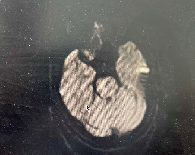

DWI

重要影像结论:脑干梗死灶。

导丝怎么扩【载药时代 球扩天下】NOVA DES®颅内药物洗脱支架在颅内富穿支区域使用体会二例!_https://www.jmylbn.com_新闻资讯_第30张

DSA

重要影像结论:基底动脉重度狭窄。